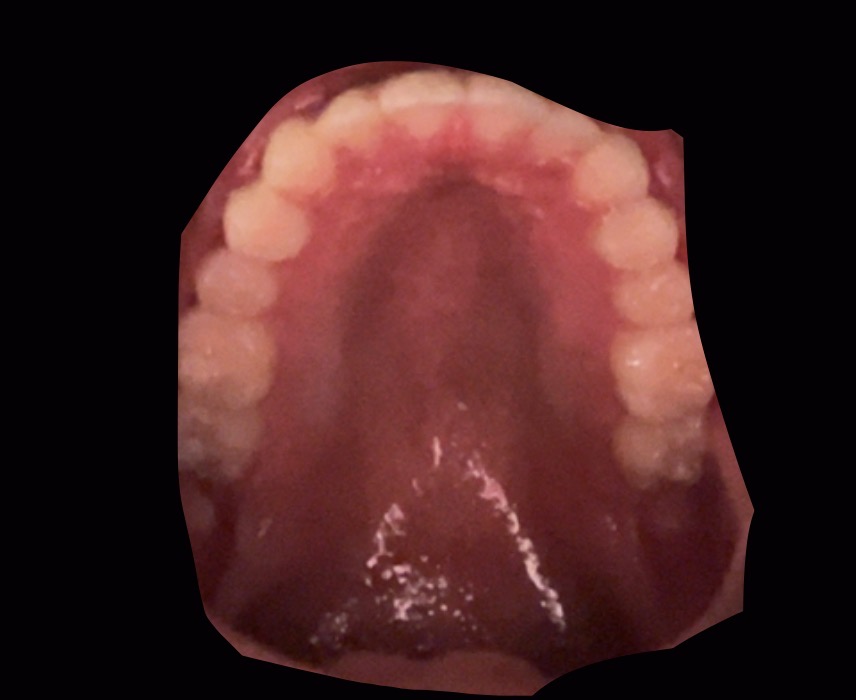

This is my palate and I can’t tell if it’s narrow or not. I feel like it is and I want an MSE. Is this narrow enough to get an MSE, or is there more larping I have to do to my orthodontist? Is there anyway I can forcibly get sleep apnea or fuck up my maxilla more so my orthodontist has to give it to me?